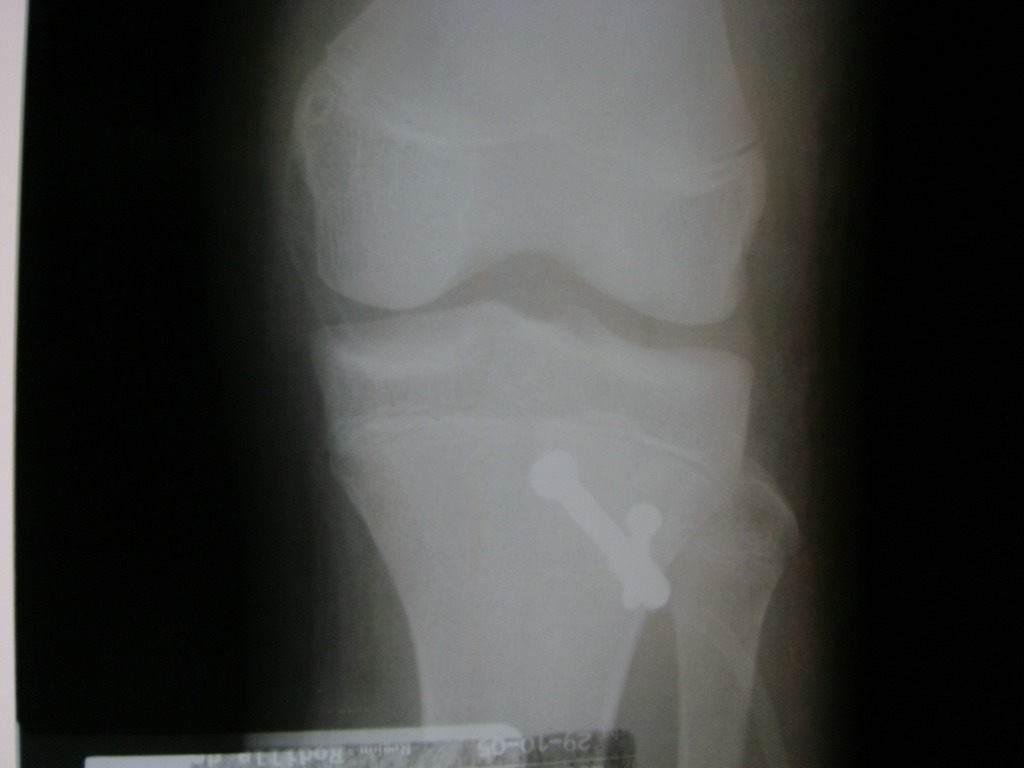

Cirugías de Calcaneo - Rodilla

La artroscopia de rodilla es un cirugía en el cual la estructura interna de la articulación es examinada ya sea para realizar un diagnostico o para realizar un tratamiento, este procedimiento se realiza utilizando un instrumento parecido a un pequeño tubo llamado artroscopio.